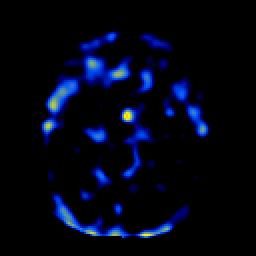

SPECT TL Study #1 -- Slice #22

[Home][Help][Clinical][Tour 1][Tour 2][Tour 3] Slice 22